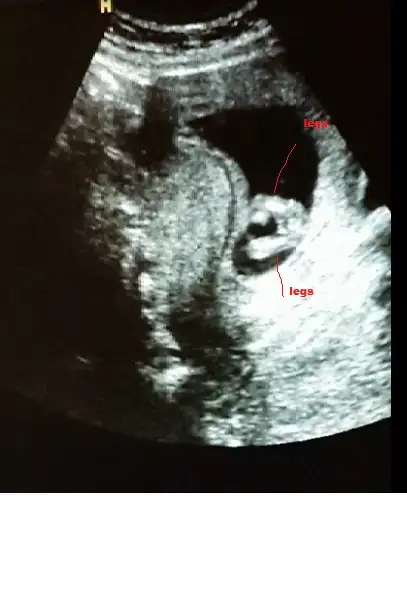

bak buda bacak arası. ama video çekmiştik sanki pipi var gibi geldi bana. acaba kordon mu o? çok kalındı zaten keşke videoyu gönderebilsem sana :).. bu arada yorumun için çok teşekkür ederim canım:KK68:

Canım kızda da erkekte de bu haftalarda çıkıntı oluyor sadece kızın çıkıntılı karşıya bakıyor erkeğin yukarı doğru senin o pipi gibi gösterdiğin karşıya bakıyor kız gibi yani yinede yanılma payı vardır mutlaka